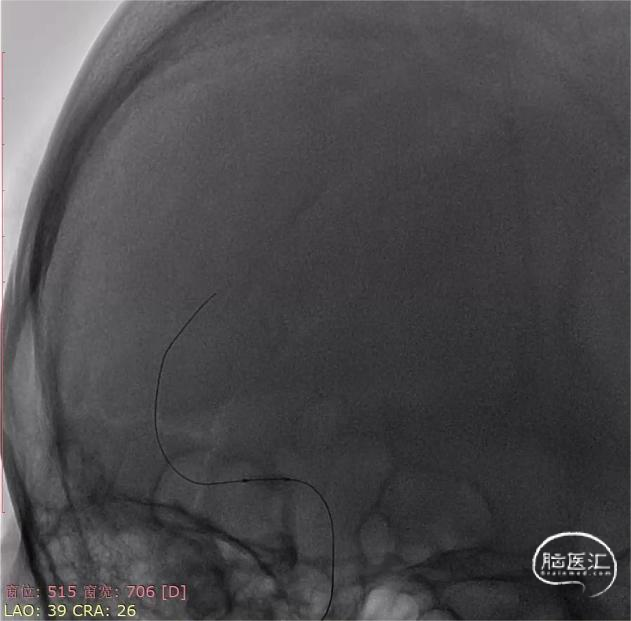

6F长鞘配合5F多功能导管,在泥鳅导丝引导下同轴技术选入右侧颈内动脉C2段,撤出导丝以及5F多功能导管,随后造影路图下将微导丝配合微导管送达右侧大脑中动脉上干M2段。6F血栓抽吸导管在微导丝配合微导管同轴引导下选入右侧大脑中动脉M1段起始,随后撤出微导丝和微导管,采用ADAPT技术持续负压抽吸,抽出一3.0mm*8.0mm暗红色血栓,再次造影提示右侧大脑中动脉复通,但可见右侧大脑中动脉M1段重度狭窄。

随后使用一次性球囊扩张导管(2.0mm*9.0mm),8个atm压力下缓慢扩张。扩张后即刻造影提示右侧大脑中动脉狭窄解除满意,前向血流eTICI3级。

观察20分钟,管腔无回缩,前向血流eTICI3级,遂结束手术。